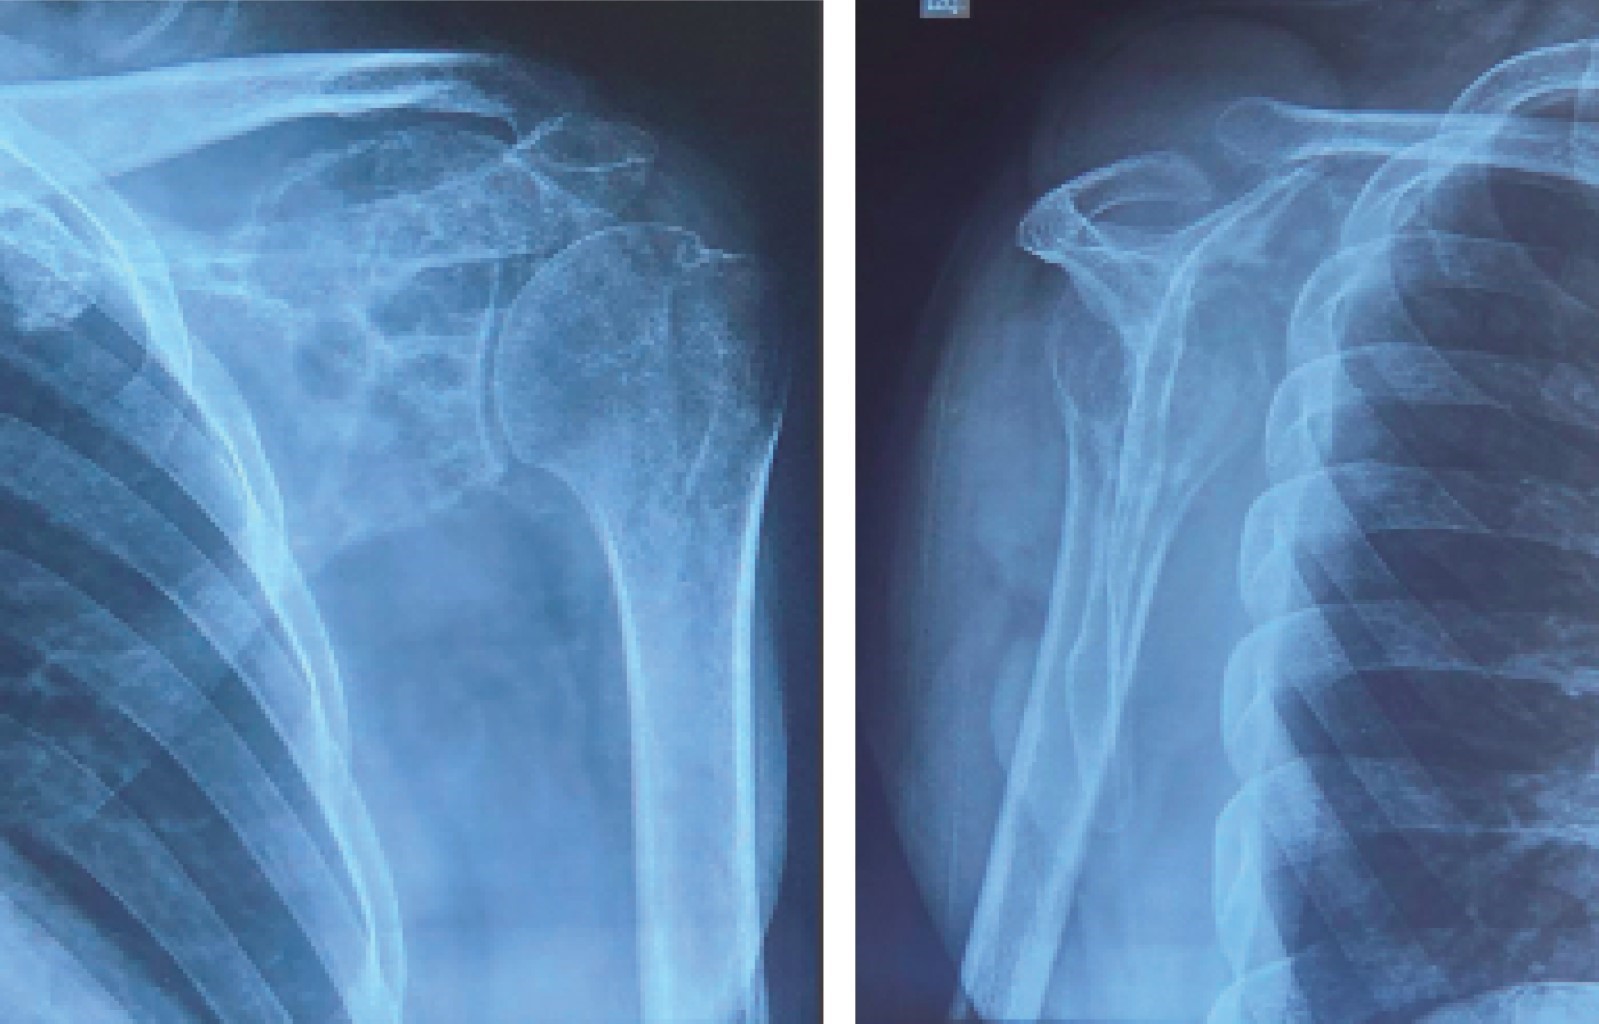

Se trata de un paciente masculino de 36 años de edad, de profesión ingeniero en sistemas, que acudió a consulta en el servicio de traumatología y ortopedia de nuestro hospital, por dolor en región escapular izquierda de dos años de evolución. Negó enfermedades crónico-degenerativas, consumo de medicamentos, alergias, fracturas y cirugías previas; niega antecedente traumático y exposición a radiación. Durante el interrogatorio directo, refirió el inicio de su padecimiento como un dolor progresivo de carácter inespecífico, localizado en la zona mencionada previamente, que lo llevó a buscar alivio con diversas sesiones de fisioterapia, las cuales no fueron fructíferas. La exploración física reveló una limitación funcional del hombro izquierdo con arcos de movilidad glenohumerales nulos, así como aumento de volumen en región de trapecio de densidad blanda, no dolorosa, con aumento de la trama vascular en la cara anterior del hombro; igualmente, en la zona de la coracoides se palpó aumento de volumen con densidad ósea, conservando la función neurovascular distal, por lo cual se solicitó una radiografía anteroposterior de hombro y una en escápula en "Y" (Figura 1), que mostró una lesión radiolúcida de comportamiento benigno hacia el borde superolateral de la escápula.

El abordaje diagnóstico del condrosarcoma necesita el uso de estudios de imagen complementarios. Las directrices actuales recomiendan radiografías simples e imágenes transversales de todo el hueso afectado (RMN) para evaluar ubicación, extensión, actividad, naturaleza cartilaginosa e identificar metástasis omitidas.1,11 Radiográficamente se observan lesiones radiolucentes; los CS de alto grado de gran tamaño muestran apariencia apolillada, en el CS grado 2 se exhibe una tumoración mal definida, con leve mineralización de la matriz, aunado a destrucción ósea permeable.1,10,14 La RMN con o sin contraste es el estándar de oro en el diagnóstico por imágenes del CS.1 En la RMN con contraste, el CS exhibe un hallazgo no patognomónico, constituido por el realce septal y periférico (en patrón de "anillos y arcos").2 En fase T1, se aprecia una señal homogénea que contrasta claramente con la señal de la médula ósea, mientras que en T2 las lesiones son típicamente brillantes; las regiones calcificadas aparecen como focos de baja intensidad de señal en los componentes condroides de alta intensidad.2 En el CS grado 2, se puede confirmar una naturaleza agresiva, al observarse puntos de destrucción cortical puntiforme con afectación de tejidos blandos.14 La tomografía computarizada es la mejor modalidad para visualizar la destrucción ósea y el patrón de mineralización de la matriz, pero no es necesaria para el diagnóstico.7 A pesar del uso de estudios de imagen, el diagnóstico depende principalmente del examen histopatológico postoperatorio de la lesión obtenida, determinando la clasificación del tumor, su estadificación, como la comprobación de márgenes libres.7,9,11